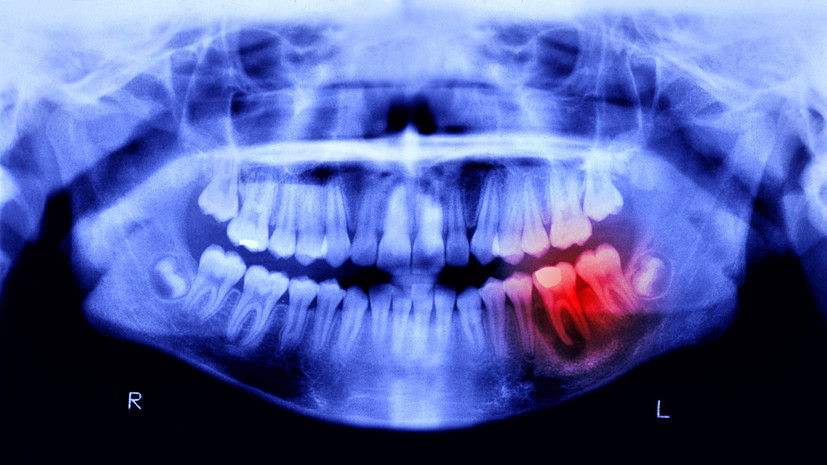

Специалист прокомментировал исследование о связи кариеса с болезнью Паркинсона

По его словам, при нарушении гигиены полости рта бактерии могут попадать в кишечник, где вырабатывают токсичное соединение имидазол‑пропионат, способное достигать мозга и провоцировать гибель дофаминергических нейронов.

Эксперт добавил, что результаты исследования открывают возможности для профилактики через стоматологическую помощь, а пока клинические приложения находятся в разработке, регулярный уход за зубами становится потенциальным способом защитить мозг.